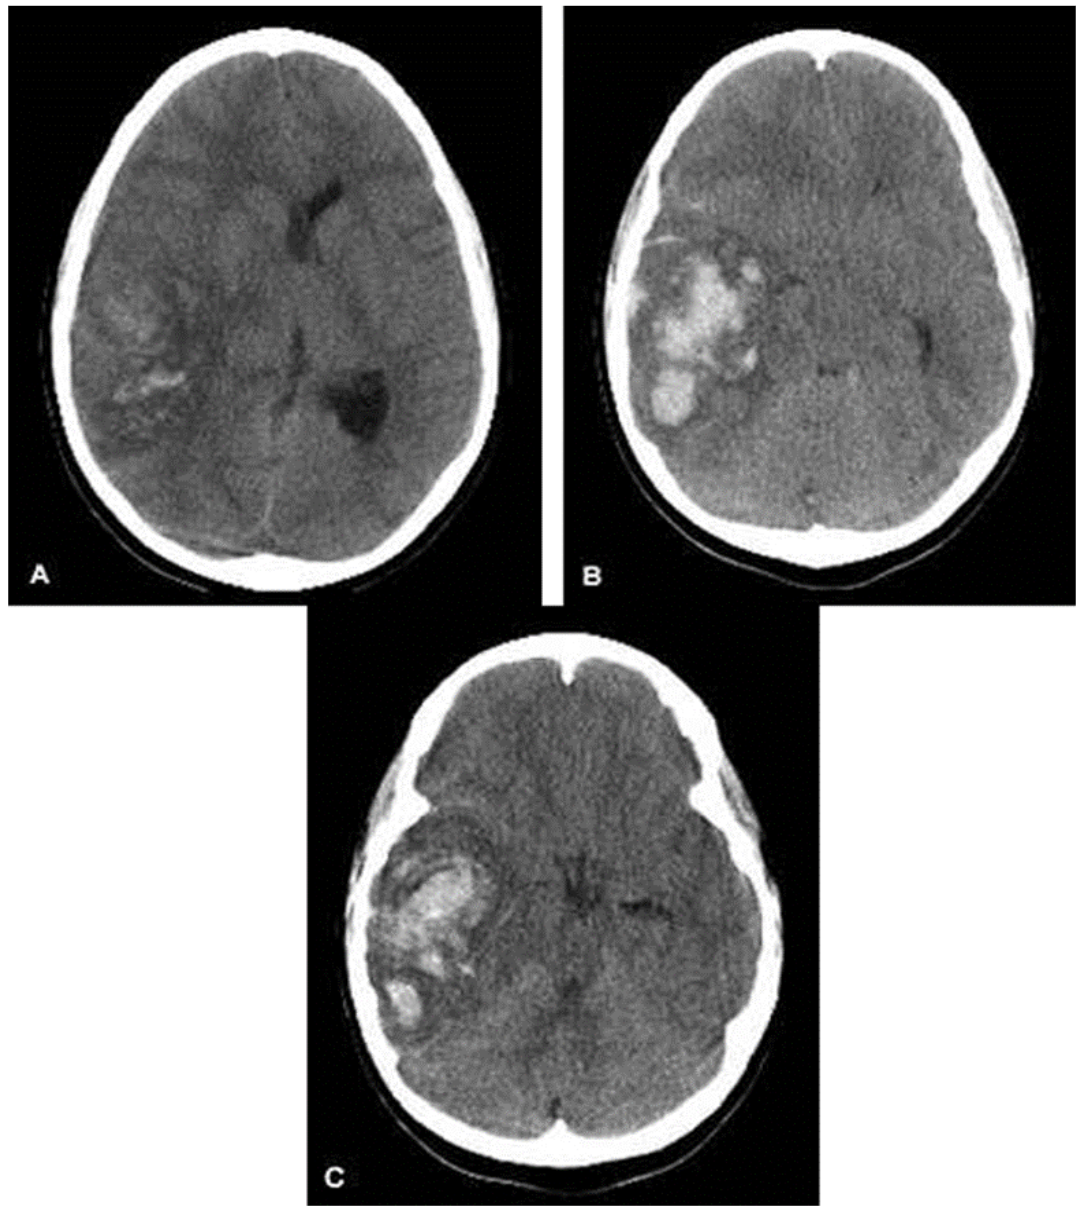

- Subdural Hematomas: Occur when there is bleeding into the space between the dura and arachnoid membranes. They appear as concave or crescent-shaped collections of blood on CT scan and can cross suture lines. These are generally caused by tears to the bridging veins between the cortex and venous sinuses. The hemorrhage occurs more slowly than in epidural hematomas, although still over a period of a few hours.

Figure: Subdural hematoma. Image courtesy of Dr. James Heilman. Image used under the Creative Commons Attribution-Share Alike 3.0 Unported license.

- Subarachnoid Hematomas: Occur when there is bleeding into the space between the arachnoid membrane and the pia mater that surrounds the brain.

Figure: Subarachnoid Hemorrhage. Image courtesy of Dr. James Heilman. Image used under the Creative Commons Attribution-Share Alike 3.0 Unported license.

- Intraparenchymal Hemorrhages: Occur when there is tearing of intraparenchymal blood vessels. Depending on the size, these can also cause mass effect and midline shift, and may be more difficult to manage surgically than extra-axial hemorrhages.

Figure: Intraparenchymal Hemorrhage. Image courtesy of MD Computed Tomography diagnostic team. Image used under the Creative Commons Attribution-Share Alike 3.0 Unported license.

When evaluating a CT scan with an intracranial hemorrhage, it is important to not only identify the type of hemorrhage, but also to note the size and whether the lesion is causing mass effect or midline shift.